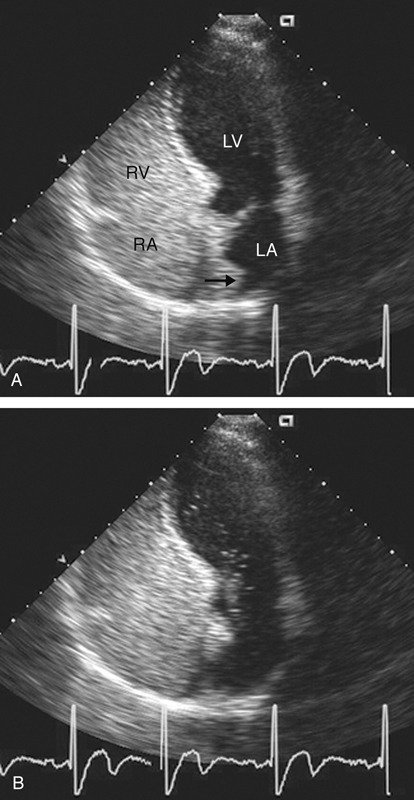

فحوصات تشخيصية لبعض امراض القلب والشرايين التاجية